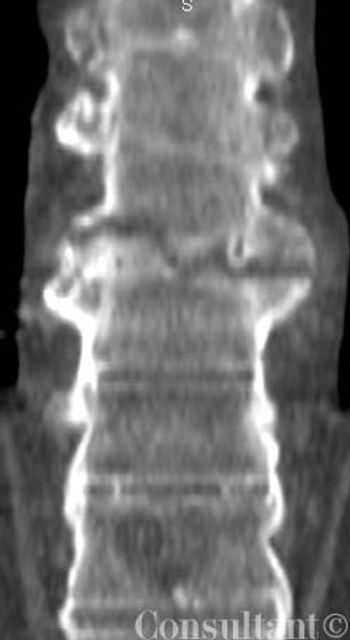

The pattern of pleural calcification and the patient's history are helpful in determining the usually remote cause of the calcification. Here, Drs Mahesh Duggal, Achal Dhupa, Krishna Badhey, and Arunabh of North Shore University Hospital of Forest Hills, NY, offer 2 cases that illustrate the importance of these data.